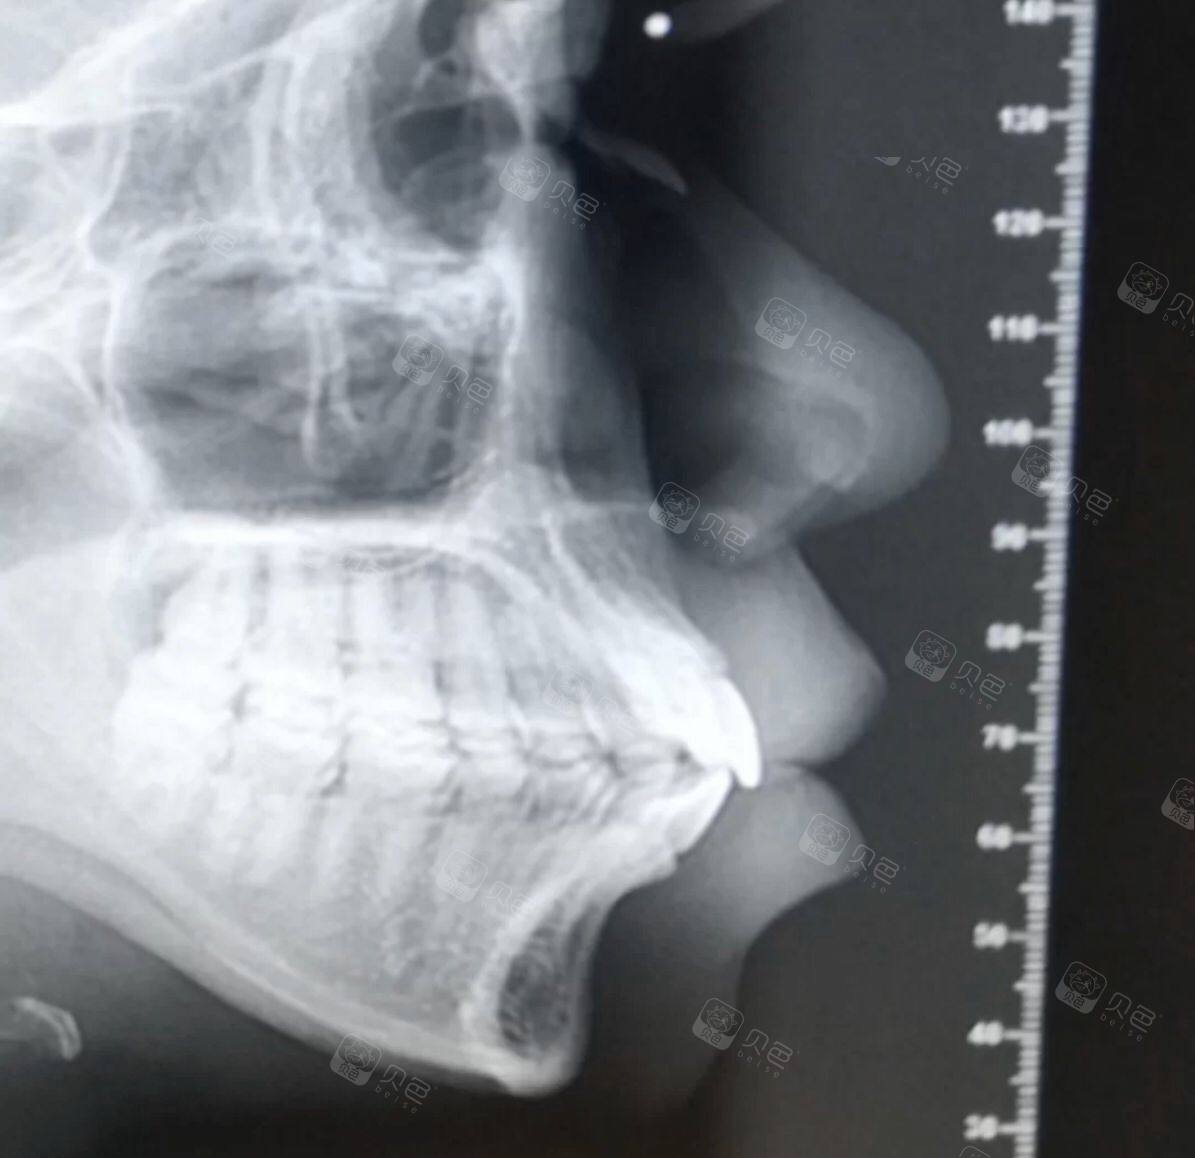

x光照(侧面)

请问这个片子牙齿是骨性还是牙性.

谁能有我这侧面牙槽骨突出

友们会看牙片吗求帮我看看这是骨性还是牙性地包天

需要正颌吗?(内附侧面照及x光)